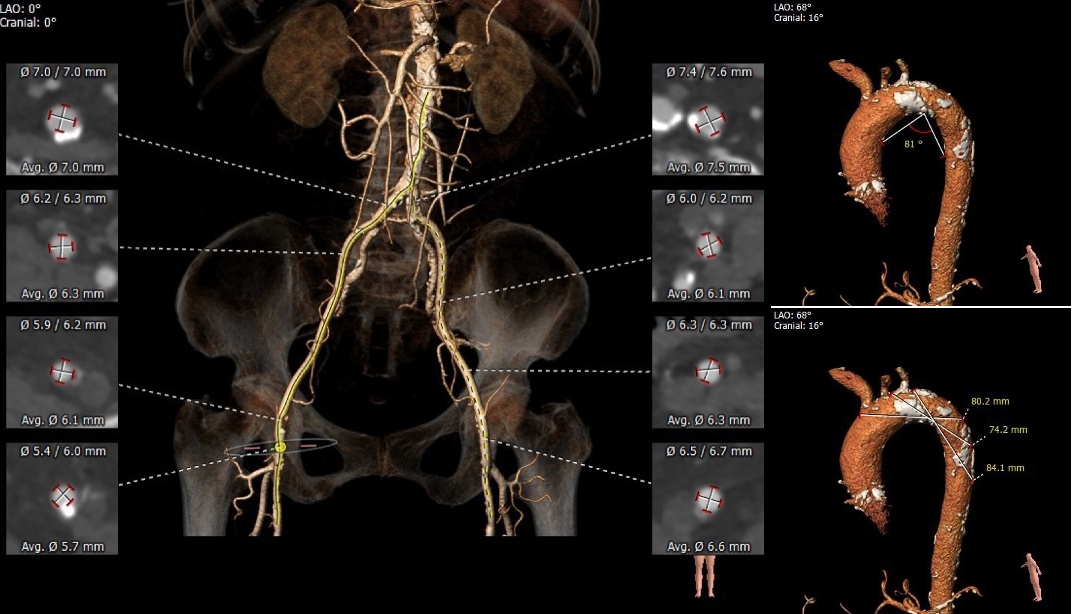

术前CT显示为三叶式主动脉瓣,瓣膜钙化、瓣叶增厚,伴左-右及左-无瓣叶融合,左右冠脉开口较低,瓣叶冗长,冠脉闭塞风险高,同时合并冠状动脉及主动脉的严重钙化。

瓣环水平夹角为52°,降主动脉全程满布钙化斑块,双侧股动脉散在钙化斑块,血管入路直径偏小,最细处仅为5.5mm。

主动脉根部测量

冠脉高度、瓣叶长度及钙化测量

瓣环上多平面测量

外周血管及主动脉弓解剖

南京市第一医院张俊杰教授团队在手术前对患者进行整体评估讨论,本例手术最大的难点在于冠脉阻挡风险高和外周血管直径偏细。根据冠脉高度、瓣叶长度、瓦氏窦宽度、钙化分布综合分析,为预防左右冠阻挡,术前预埋Guidezilla保护。

同时,改用左侧股动脉为主入路,右侧辅助入路。球囊扩张采用左冠切线位角度(LAO 18°CRA 26°),并用较小的18mm球囊预扩张。预装AV23瓣膜,瓣膜释放体位左右重合体位(RAO 20°CAU12°),释放深度在4-5mm。球囊扩张和瓣膜释放时,密切关注冠脉灌注情况。